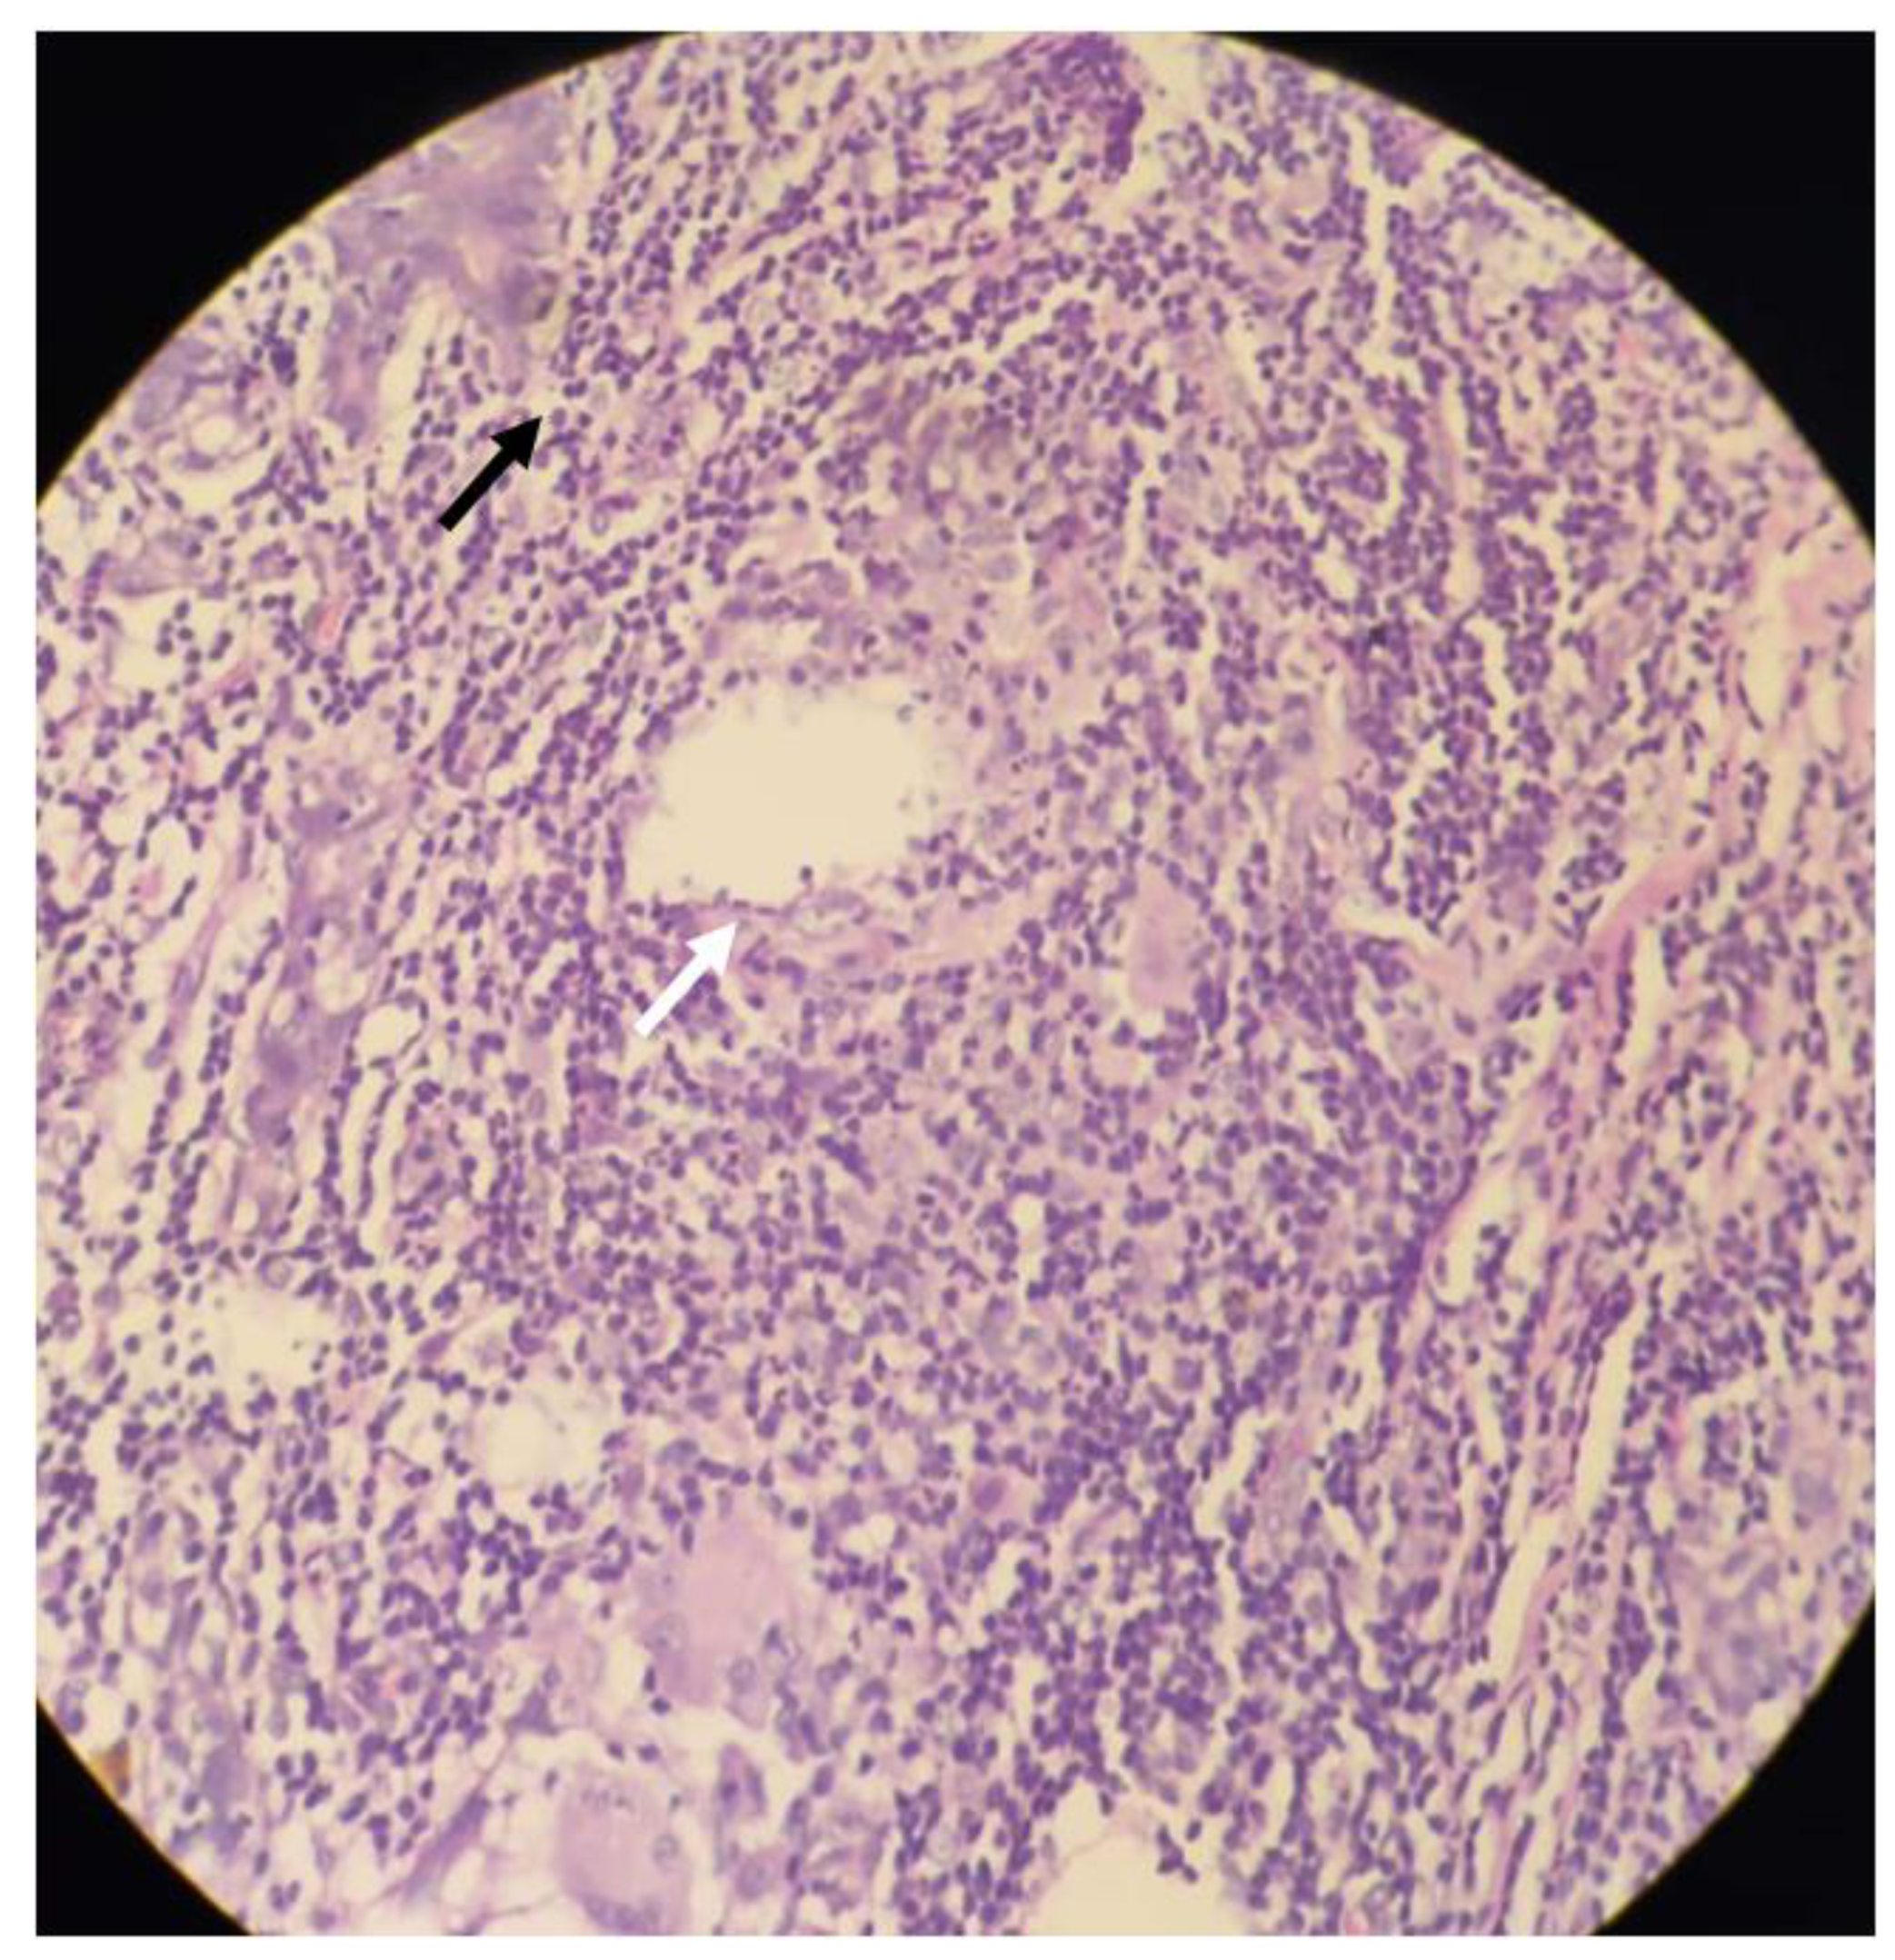

2. Case Presentation